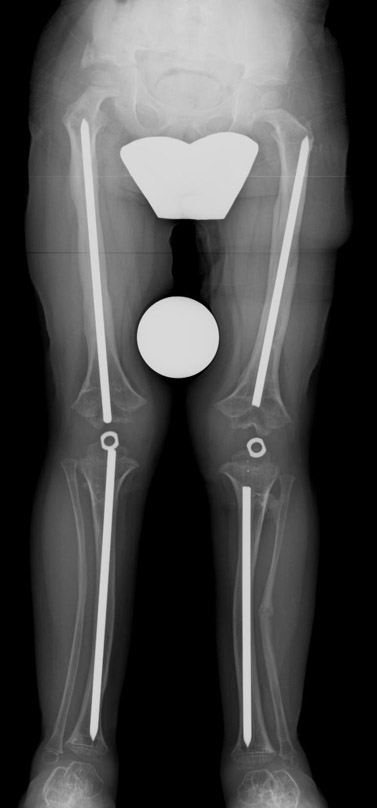

12-14 yaşları arasında Her iki tibiada toplam 10-15cm boy uzatma (iki seviyeli uzatma) Proksimal tibianın varus deformitesini proksimal osteotomi ile düzeltilmesi Distal tibianın varus deformitesi distal osteotomi ile düzeltmesi Distal tibianın varus deformitesi distal osteotomi ile düzeltmesi Boy uzatmanın sonunda lateral kollateral ligamentin gerilmesi Ortalama eksternal fiksasyon tedavi süresi = 8-10 ay

13-15 yaşlar arasında Her iki humerusu (kol) 8-12 cm boy uzatma Dirseklerin fleksiyon deformitesini düzeltme Ortalama eksternal fiksasyon tedavi süresi = 6-8 ay Alt uzuvların iki uzatması arasında üst uzuvlar uzatılarak alt uzuvların dinlenmesi sağlanmış olur. Cihaz çıkartıldıktan sonra en erken ikinci uzatmaya başlama süresi 6 aydır. Bilateral femoral uzatmalarda uzatma fazı sırasında hastanın yürümesi mümkün değildir. Ayakta durmaya sadece hasta transferi sırasında izin verilir. Uzatma fazında ambulasyona sadece tekerlekli sandalye ile izin verilir. Konsolidasyon fazında ise tedrici olarak daha fazla yük verilmesine ve cihazın çıkmasına yakın serbest yürümeye izin verilir. Bilateral tibial uzatmalarda ilk günden itibaren yürüteç veya koltuk değneği ile hastanın yük vermesine izin verilir. Uzun gezintiler tekerlekli sandalye ile yapılmalıdır. Bilateral humeral uzatmalarda hemen hemen hiçbir aktivite kısıtlaması yoktur. Uzatma süresince her iki haftada bir yapılan takiplerde kantitatif duyusal sinir testleri doktor tarafından yapılmalıdır. Bu gelişmekte olan sinir sorunlarını klinik olarak ortaya çıkmadan yakalamaya izin verir. Femoral ve humeral uzatmalarda çok nadir görülmesine rağmen tedavi edilmedikleri durumda düşük ayağa (ayağı yukarı çeken kasları innerve eden sinirin felci) neden olabilirler. Eğer erken tespit edilir ve uzatmanın hızı azaltılırsa, sinir problemi genellikle kendiliğinden düzelir ve uzatmaya düşük hızda devam edilir. Uzatmada yavaşlamaya rağmen sinir problemi devam ederse sinirin cerrahi olarak gevşetilmesi gerekir. Bu işlem 1cm’ lik bir kesi ile yapılabilen ve hastanede bir gece kalmayı gerektiren küçük bir işlemdir. Bu ameliyat el bileğinde sinir sıkışması (karpal tünel sendromu) için yapılana benzerdir.

Vaka 2